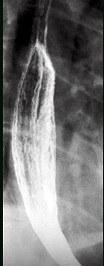

- 单项选择题男,34岁, 胸骨后烧灼痛1周,伴吞咽痛, 餐后平卧时加剧,食管钡餐检查如图, 应诊断为  (    )

- C、反流性食管炎